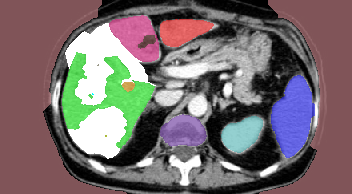

We pursued a more challenging structure, see Fig.19(a). The objective in this case was to segment the liver into three segments and any tumors inside them separately. Due to the large overlap between color models and the complex structure, having Hedgehog priors was not enough for QPBO or a-exp to converge to an adequate solution, see Fig.19(c-e). Path-Moves was able to achieve good results by avoiding local minima as in Fig.19(c). Furthermore, Path-Moves guarantees full labeling in contrast to QPBO, which left of the pixels unlabeled in Fig.19(d).

In conclusion, our results empirically show that for a general tree a-exp converges to weak local minima, and QPBO is unpredictable in terms of being able to label all pixels. Path-Moves which uses an effective multi-label expansion move, labels all pixels and easily avoids weak local minima that a-exp is prone to.